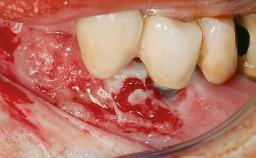

A 35-year old female patient was referred to the Department of Oral Surgery and Stomatology at the University of Bern, Switzerland, for examination of an implant site that had exhibited clinical signs of slightly delayed wound healing. In addition, the referring clinician found no evidence for a facial bone wall when she raised a flap to gain access to the implant for abutment connection. Four months earlier, she had inserted a bone-level implant in a single-tooth gap, where the lateral incisor had been extracted due to a chronic periapical lesion on the mesial aspect of the root. Implant placement was combined with simultaneous bone augmentation using deproteinized bovine bone mineral (DBBM, Bio-Oss®; Geistlich, Wolhusen, Switzerland) and a collagen membrane (Bio- Gide®; Geistlich), followed by primary wound closure. The patient also provided the postsurgical radiograph that displayed the implant with a 3.5-mm healing cap.